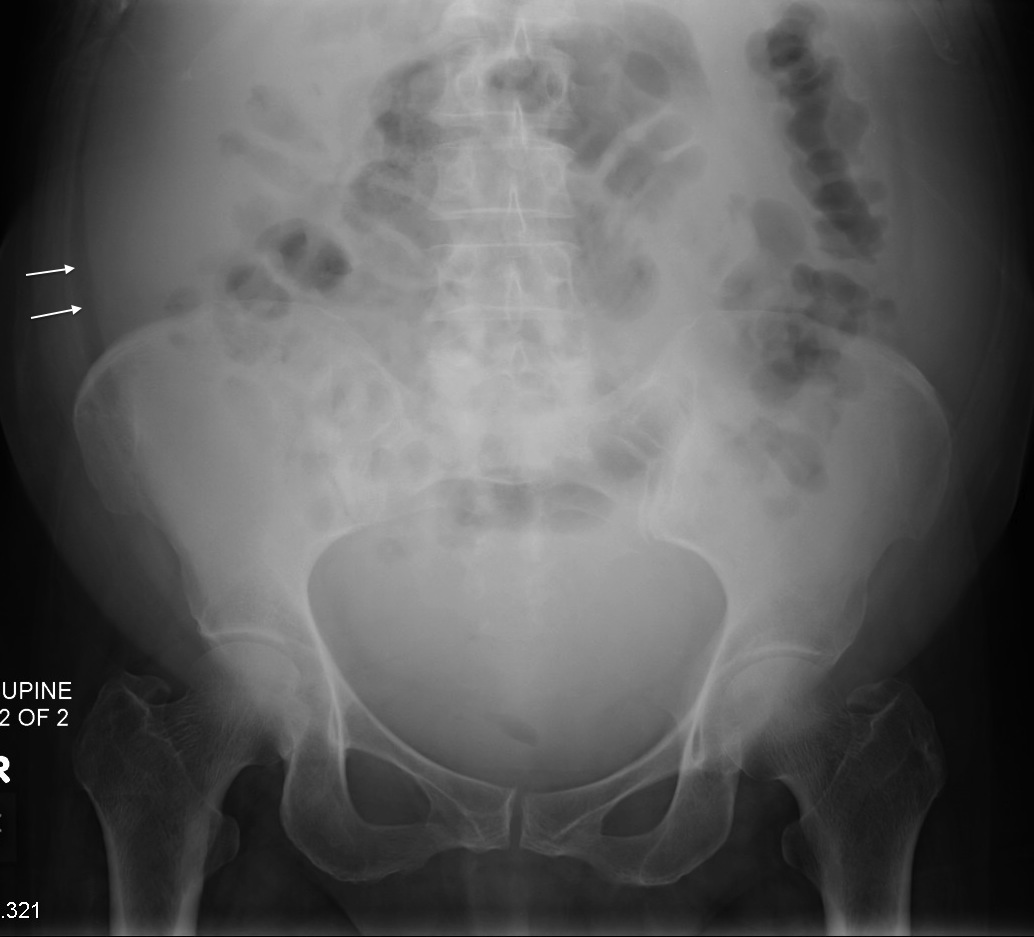

Learning Radiology Ascites Gelatinous Ascites Fluid Positive for mucin and atypical malignant cells. Pseudomyxoma peritonei (pmp, orpha26790) is a clinical syndrome characterized by progressive dissemination of. Imaging is key to the initial diagnosis, revealing typical findings on us, ct and magnetic resonance imaging such as. The fluid’s viscous appearance prompted consideration of pseudomyxoma peritonei (pmp) over more. Imaging is key to the initial diagnosis, revealing typical. Gelatinous Ascites Fluid.